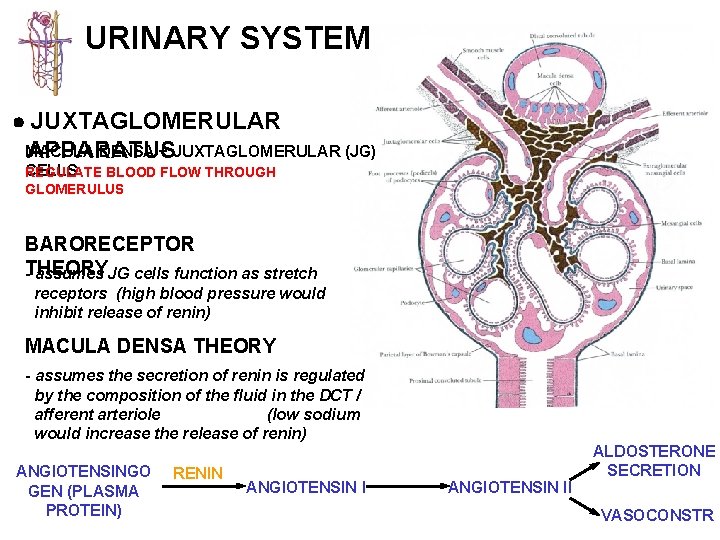

URINARY SYSTEM JUXTAGLOMERULAR MACULA DENSA + JUXTAGLOMERULAR (JG) APPARATUS CELLS REGULATE BLOOD FLOW THROUGH GLOMERULUS MACULA DENSA - cells located in the DCT in close contact with the glomerulus and the afferent and efferent arterioles JG CELLS - specialized smooth muscle cells in the wall of the afferent arteriole which contain and secrete RENIN to regulate blood flow through the glomerulus ANGIOTENSINGO GEN (PLASMA PROTEIN) RENIN ANGIOTENSIN II ALDOSTERONE SECRETION VASOCONSTR

URINARY SYSTEM JUXTAGLOMERULAR MACULA DENSA + JUXTAGLOMERULAR (JG) APPARATUS CELLS REGULATE BLOOD FLOW THROUGH GLOMERULUS BARORECEPTOR THEORY - assumes JG cells function as stretch receptors (high blood pressure would inhibit release of renin) MACULA DENSA THEORY - assumes the secretion of renin is regulated by the composition of the fluid in the DCT / afferent arteriole (low sodium would increase the release of renin) ANGIOTENSINGO GEN (PLASMA PROTEIN) RENIN ANGIOTENSIN II ALDOSTERONE SECRETION VASOCONSTR